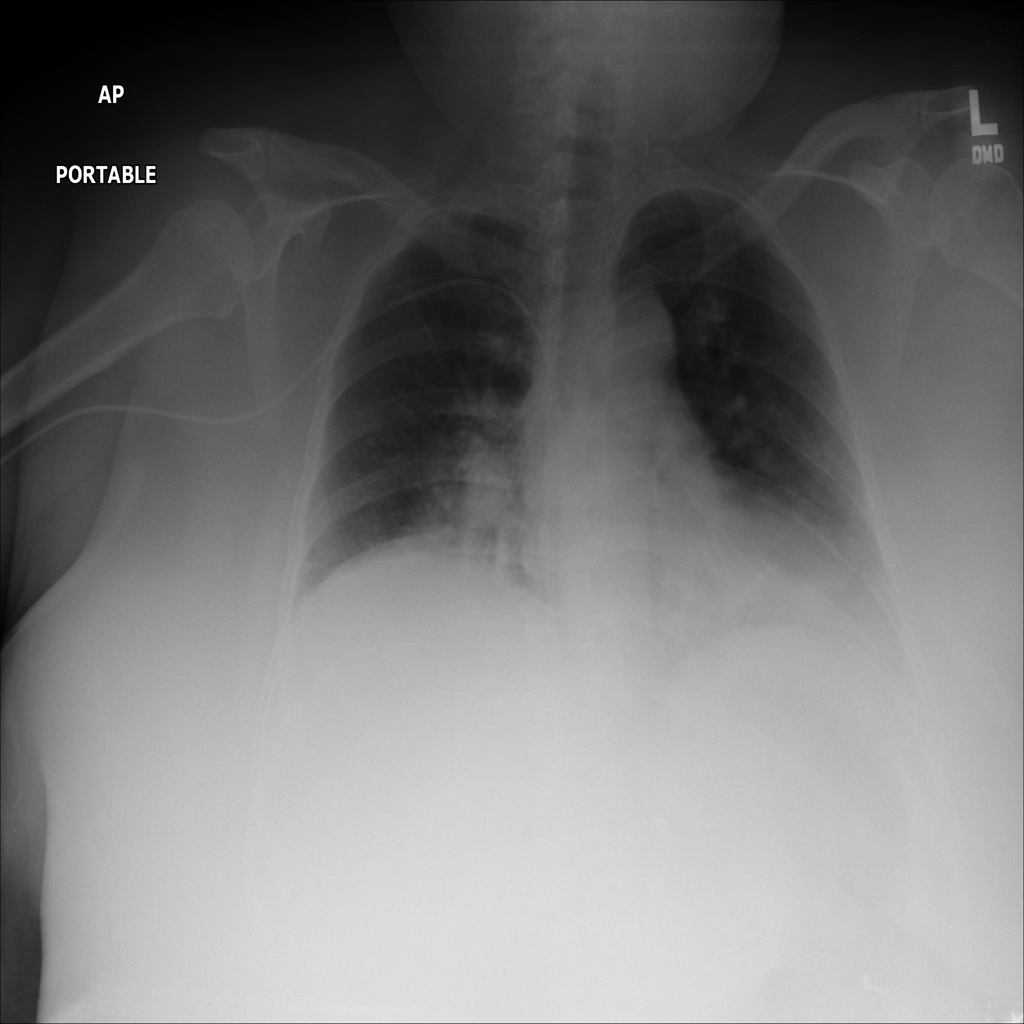

PAT-B9C3 · IMG-000Atelectasis

PAT-B9C3 · IMG-000

AP